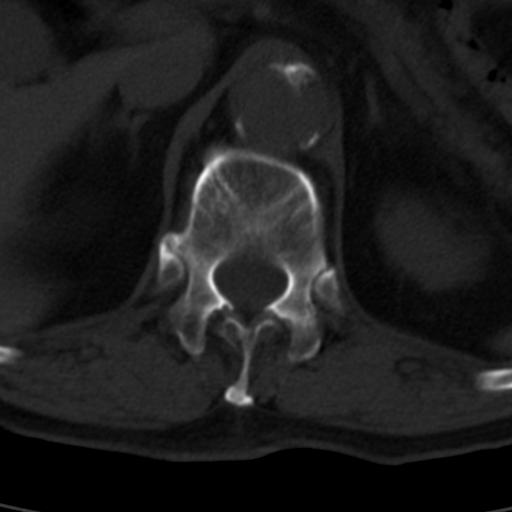

男性 82 主动脉夹层 请大家看看椎体是什么改变啊

腰椎退行性变,明显的骨赘形成,所指低密度灶为正常松质骨。